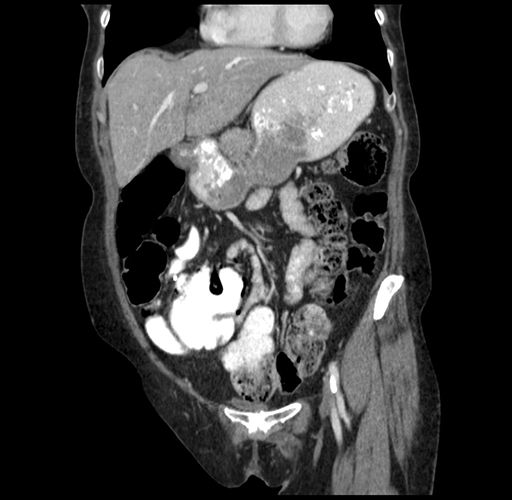

Pre-Chemo: Coronal Venous

Coronal Venous

Imaging analysis

Based on your CT findings, which issue(s) would give reason for "planned slowing down moment(s)" in this case?

Considering a standard right hepatectomy procedure, what step(s) of the operation would you do differently in this case?